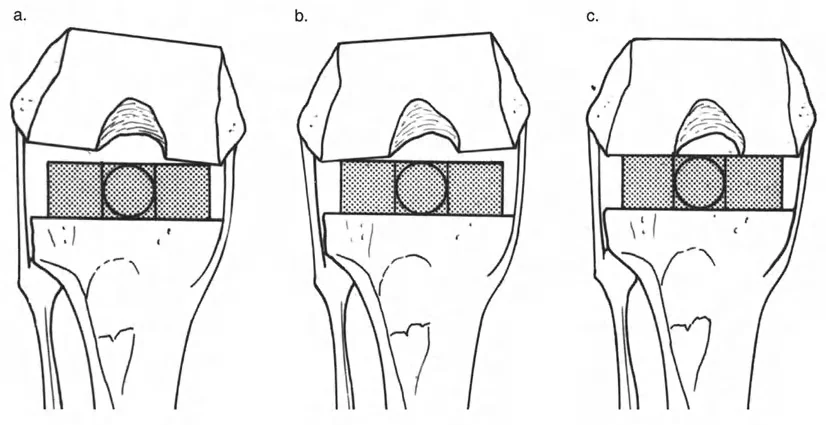

- استبدال المفاصل في حالات التشوه الشديد

التشوهات الديناميكية هي اختلالات وظيفية تتأثر بموقع المفصل في الفراغ، ووظيفة العضلات، والأهم من ذلك، الطول الفعلي والتوجيه المكاني لأذرع الرافعة الهيكلية أثناء الحركة. على عكس التشوهات الثابتة التي تكون موجودة بغض النظر عن الحركة، فإن التشوهات الديناميكية تظهر بوضوح أو تتفاقم عندما يحاول المريض أداء حركة معينة، مثل المشي أو الوقوف.

في حين أن التشوهات الديناميكية تُناقش غالبًا في سياق أمراض الأعصاب والعضلات لدى الأطفال، فإن المبادئ البيوميكانيكية التي تحكمها تنطبق عالميًا على إعادة بناء العظام لدى البالغين. يشمل ذلك سيناريوهات إعادة البناء المعقدة للغاية، مثل استبدال مفصل الركبة الكلي (TKR) واستبدال مفصل الورك الكلي (THR) المرتبطة بالانحرافات الشديدة خارج المفصل. إن فهم الأذرع الرافعة هو المتطلب الأساسي لإتقان هذه التقنيات المتقدمة في جراحة المفاصل وقطع العظم، وهو ما يتقنه الأستاذ الدكتور محمد هطيف في ممارسته اليومية.

بشكل خاص، يصف خلل وظيفة الذراع الرافعة حالة سريرية تتشوه فيها أذرع الرافعة الداخلية و/أو الخارجية بسبب سوء محاذاة العظام، أو التشوهات الالتوائية، أو تيبسات المفاصل الموضعية.